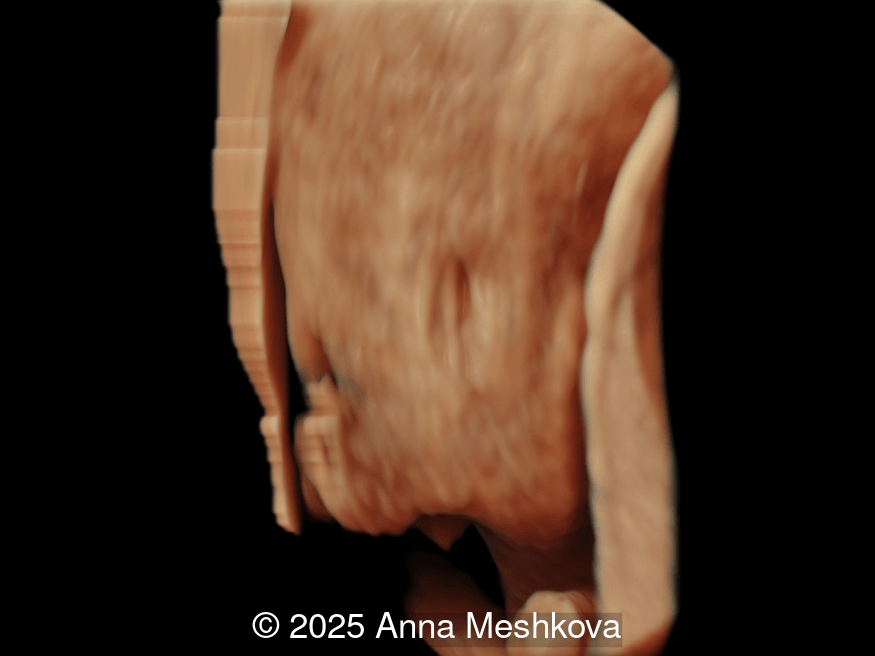

• Image 1:  Transverse section of the brain at the level of choroids. Subtle supporting sign of relatively large choroid plexuses and low surrounding cerebrospinal fluid known as the "dry brain" sign.

3D reconstruction of the spinal defect in the lumbosacral region at 13 weeks gestation

Image 1 3D reconstruction of the spinal defect in the lumbosacral region at 13 weeks gestation